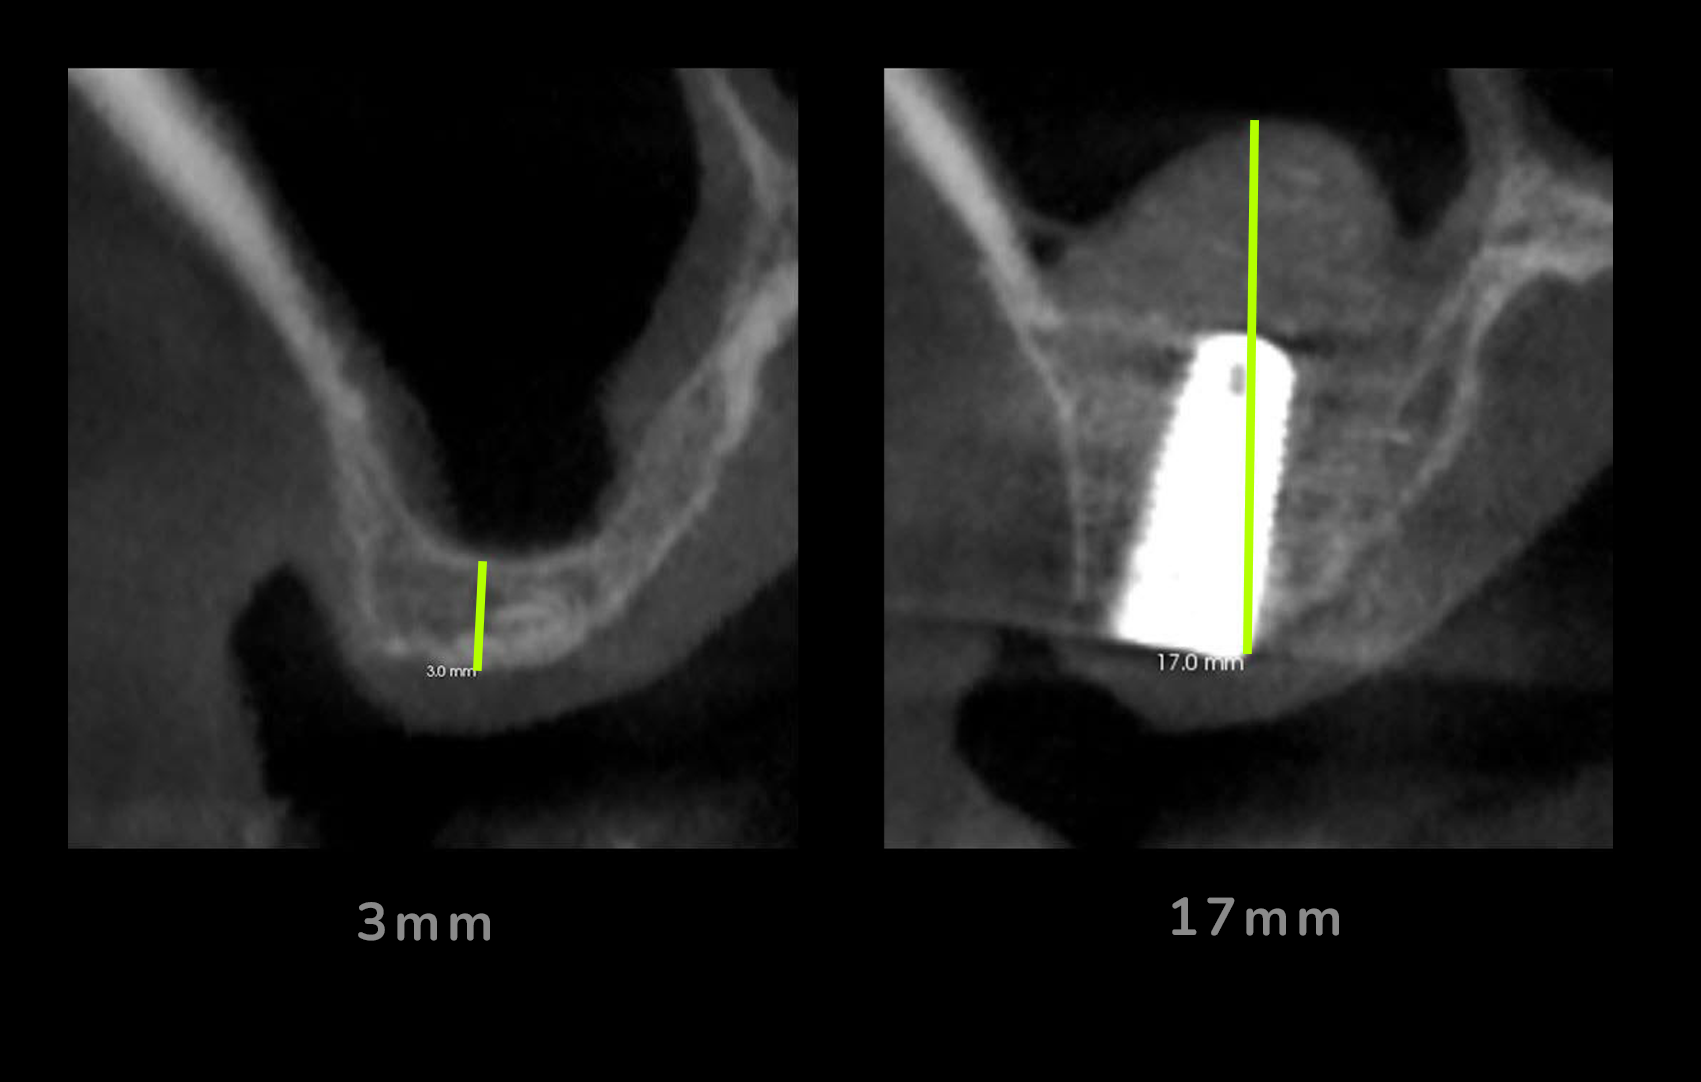

La única manera de saberlo de forma exacta es a través de un especialista que evalúe tu estructura ósea mediante un examen clínico y una radiografía o tac 3D de tus maxilares con la que se determina si tienes suficiente hueso para un implante dental estándar o si requieres algún procedimiento de injerto de hueso.

Cuando debemos colocar implantes dentales en zonas de la boca donde hay muy poco hueso es necesario fundamental realizar una correcta regeneración ósea antes de colocar el implante.

El volumen de hueso necesario para un implante dental varía según cada caso. De forma general, decimos que hay poco hueso cuando el ancho o el alto del hueso no es suficiente para soportar y rodear de hueso un implante dental.